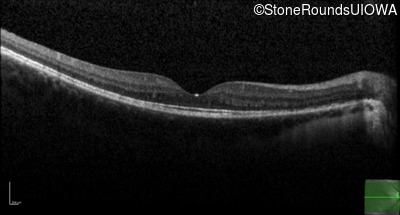

Optical Coherence Tomography - Left - 20/50

Exemplar / OCT Stack